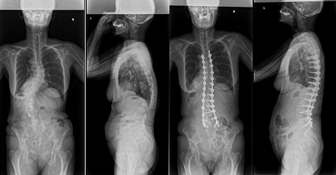

骨切りを併用した後方矯正固定術

せぼねの変形が大きかったり、再手術の場合には癒合してせぼねの骨切りを行い、再度矯正固定を行う場合があります。

5時間前後の長時間の手術となります。入院期間は小児患者様で2週間程度、大人の患者様では3週間程度で場合によってはリハビリテーション病院へ転院をしていただき、さらにリハビリテーションを行います。